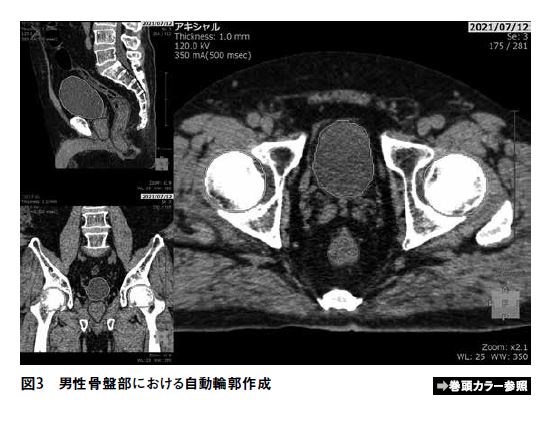

頭頸部、骨盤部領域および体幹部領域について、自動輪郭作成を行なった例を図1~3に示す。また、自動輪郭作成機能を用いて描出した輪郭と、医者により描出された輪郭との一致度(DICE 係数)を表2~4に示す。体幹部領域において、臨床に使用した治療計画に医師による輪郭描出がない場合、もしくは自動輪郭作成が正常に動作しなかった場合(心臓、肝臓で2例ずつ見られた)は評価から除外している。脊髄、直腸、心臓については上縁もしくは下縁の設定に差異があり、視神経は体積が非常に小さくスライス厚などの影響を受けやすいためDICE係数はやや小さい値を示しているものの、その他のリスク臓器については平均値および中央値でおよそ0.8~0.9となっており、高い一致度を示していることがわかる。また直腸に関してはガスが溜まっている場合は自動輪郭の精度はやや悪化するようである。肝臓については体積が大きく輪郭描出にも時間を要するが、自動で輪郭作成ができるような治療計画装置は少ない印象がある。SYNAPSE Radiotherapyは肝臓も良い精度で自動輪郭作成が可能である点は非常に評価が高いと感じる。